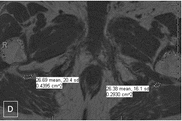

Zoomed images showing the fat fraction measurements. Zoomed image showing the sciatic nerves and their measurements at level A (figure A and B) and level B (figure C and D). (GIF 6 kb)